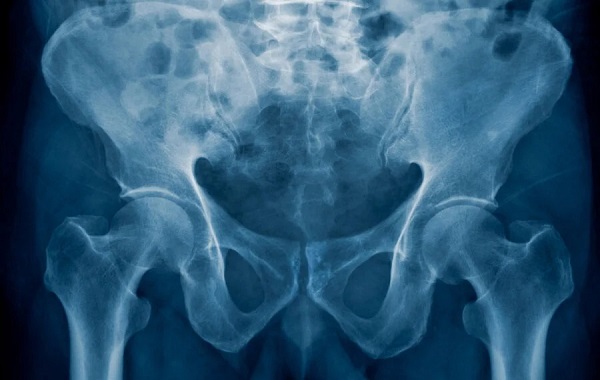

What makes us human? It’s all in the hips

After all, its design makes it possible for humans to walk upright on two legs (unlike our primate cousins), and it makes it possible for mothers to give birth to babies with heads big enough to accommodate large brains. On an anatomical level, the pelvis is well understood, but relatively little is known about exactly how and when it takes shape in a developing fetus.

Compared with chimpanzees and gorillas, the shorter and wider orientation of our pelvic blades allow humans to walk and balance upright without having to shift weight forward and use our knuckles for stability and balance. It also helps increase the size of the birth canal.